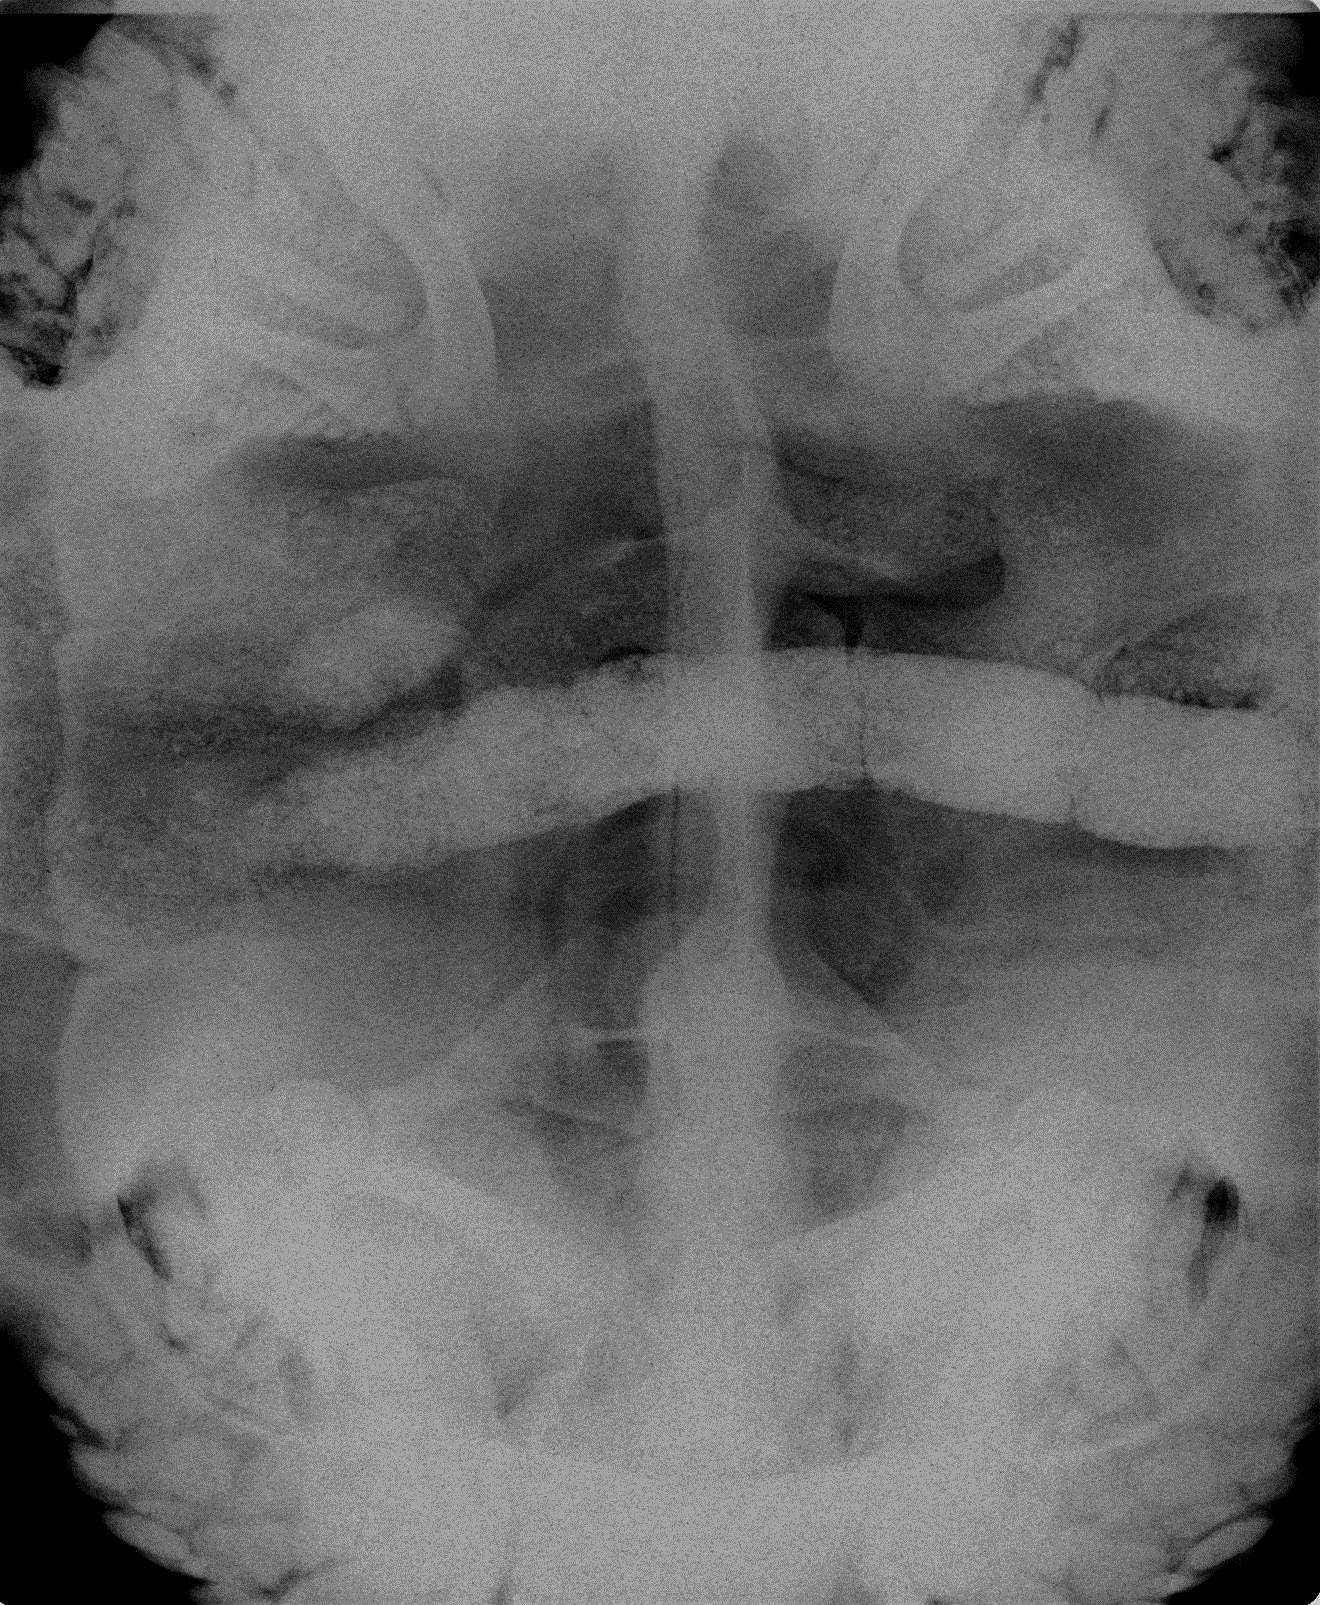

そしてこの日、卵の確認のため再びレントゲン検査をすることに。

そしてレントゲンの結果...

見事全卵産みきっていました!